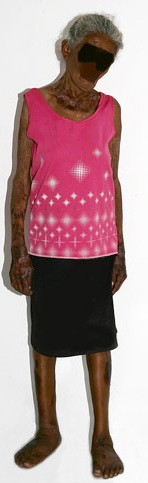

The word "pellagra" is derived from two Italian words, "pelle," meaning "skin," and "agra," meaning "sharp burning" or "rough." Although primarily ascribed to niacin (vitamin B3) deficiency, other vitamin deficiencies or protein

malnutrition appear integral to the development of the pellagra symptom complex. Presenting as cutaneous lesions, gastrointestinal symptoms, and mental changes, pellagra has been ascribed the acronym of the three Ds: dermatitis, diarrhea, and dementia. In the United States, the enrichment of whole-wheat flour with niacin has almost eliminated pellagra, but it is still prevalent in countries such as Mexico and some African nations where cornmeal is the main constituent of the diet, as well as in displaced populations . Pellagra in the United States and Europe is seen mainly in chronic alcoholics and in patients with anorexia nervosa, malignant gastrointestinal tumors, and intestinal parasitosis . Its appearance in carcinoid syndrome is believed to reflect a depression of endogenous niacin production by tumor cell diversion of tryptophan toward serotonin . Pellagra has also been reported in patients receiving isoniazid, pyrazinamide, ethionamide, azathioprine, chloramphenicol, and anticonvulsants . Isoniazid, a structural analogue of niacin, can cause suppression of endogenous niacin production.

Three basic skin eruptions occur in pellagrins . The first is a photo-induced eruption that is intensely erythematous and subsequently exfoliates to yield a hyperpigmented residuum. The second eruption comprises painful erythematous erosions in genital and perineal areas possibly induced by pressure, heat, and trauma . The increased skin fragility may reflect aberrations in the collagen and elastic fiber content of the skin. Pellagrins may develop a seborrheic dermatitis-like rash involving the face, scalp, and neck. Oral manifestations include beefy, red, cracked lips and a fissured or smooth, red, sore tongue . Among the neurologic symptoms are dementia, psychosis, anxiety, defective memory, burning sensations, sudden attacks of falling, dizziness, and headaches. A cause of sudden death is central pontine myelinolysis .